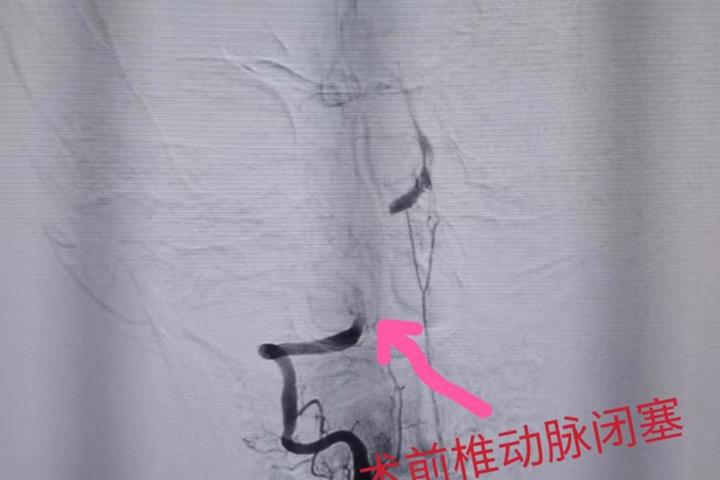

生死竞速!佛冈人医神经内科成功救治急性脑卒中患者